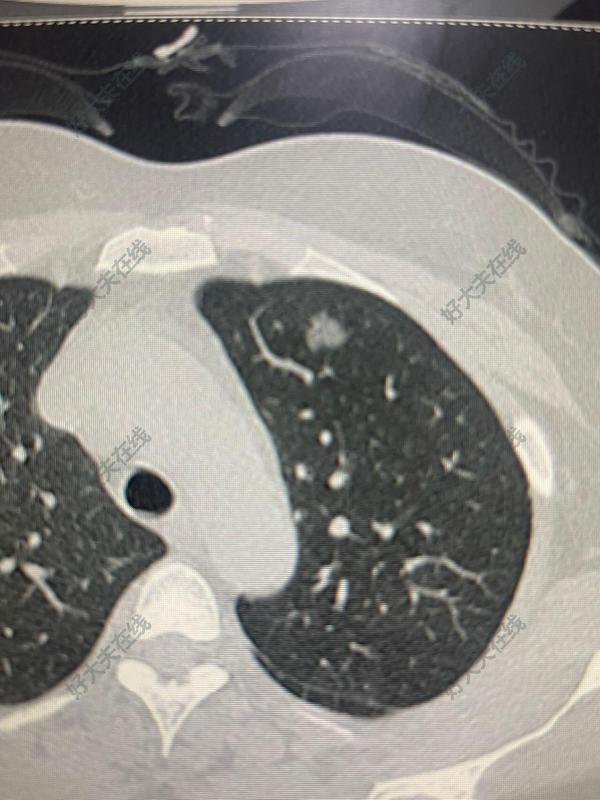

治療前患者女性,51歲,于2022年3月發(fā)現(xiàn)左肺上葉磨玻璃結(jié)節(jié),大小約11mmx10mm,由于患有腎病綜合征,身體虛弱,蛋白低,在醫(yī)生和家屬的綜合考量下選擇了肺結(jié)節(jié)射頻消融。治療中這是消融后的圖片,出現(xiàn)了明顯的暈癥,消融范圍達(dá)到了要求。無氣胸,無出血,病人無不適。治療后治療后20月這是術(shù)后20個(gè)月后復(fù)查的胸部ct,病灶完全吸收,僅留下一個(gè)條索,復(fù)查胸部,腹部ct,未見明顯腫大淋巴結(jié)。病人感覺良好。那么什么人適合射頻消融呢?1.無法手術(shù)切除者:因高齡、心肺功能差等無法耐受手術(shù)的患者。2.術(shù)后復(fù)發(fā)或多原發(fā)結(jié)節(jié):肺癌術(shù)后殘留或新發(fā)結(jié)節(jié),或多發(fā)肺結(jié)節(jié)需保留肺功能者。治療后4天這個(gè)是術(shù)后4天復(fù)查的胸部ct,輪廓更加清晰了治療后即刻這那么什么人適合射頻消融呢?1.無法手術(shù)切除者:因高齡、心肺功能差等無法耐受手術(shù)的患者。2.術(shù)后復(fù)發(fā)或多原發(fā)結(jié)節(jié):肺癌術(shù)后殘留或新發(fā)結(jié)節(jié),或多發(fā)肺結(jié)節(jié)需保留肺功能者。